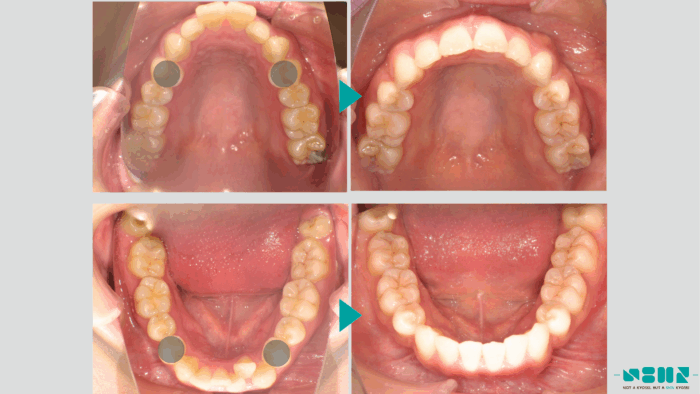

治療の方針

口元を下げて”横顔をスッキリさせたい”とのことでしたので、上下左右第一小臼歯(合計4本)の抜歯し、口元を下げるスペースを確保する準備を行いました。

ある程度、歯並びのガタガタが改善されたら、抜歯した隙間を閉じる作業を行い、その結果口元が下がりました。最後にかみ合わせの調整を行います。

治療後

矯正治療によって歯並びを整えた結果、次のような変化が見られました。

- 前歯の突出が改善

- 口元のバランスが整う

結果として、横顔の印象にも変化が見られました。※治療の効果には個人差があります。

【症例詳細】

主訴:出っ歯が気になる

診断名:上顎前突

初診時年齢:27歳

使用装置:表側ワイヤー矯正・マウスピース矯正装置(インビザライン)

抜歯部位:上下左右第一小臼歯

治療期間:2年9ヶ月

費用:¥900,000(税込¥990,000)

リスク・副作用:痛み、歯根吸収、歯肉退縮、虫歯、後戻り